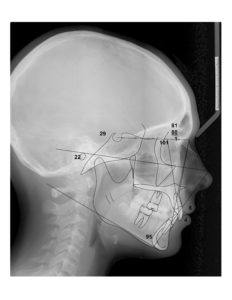

A 13-year-old female presents with a chief complaint that “My teeth aren’t in.”